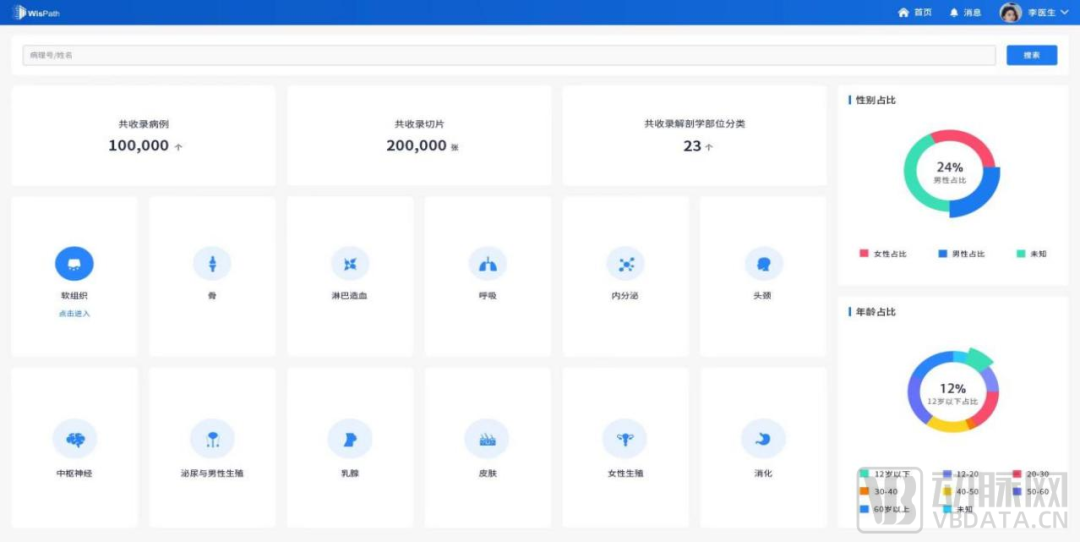

数字化病理科建设模块介绍

数字化建设模块图

来源:蛋壳研究院